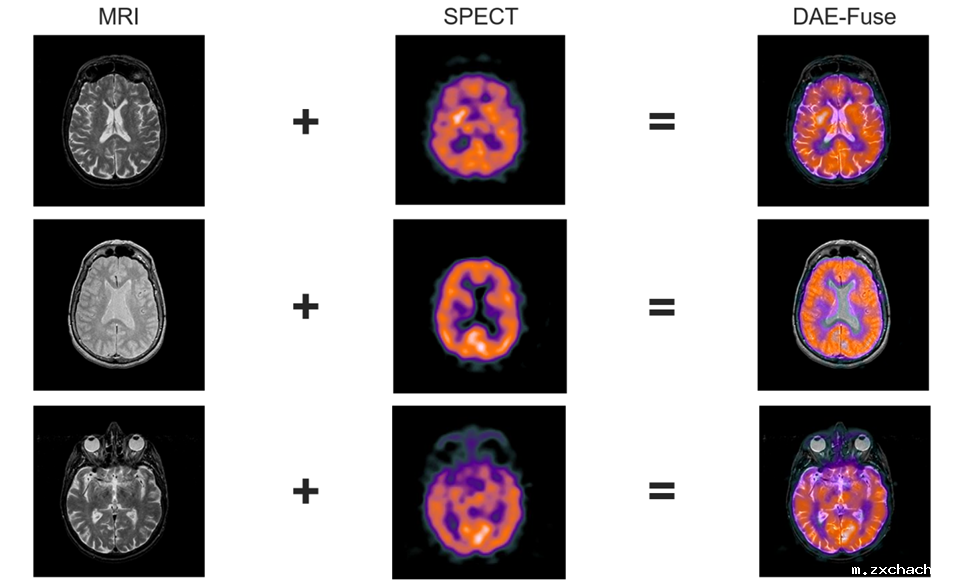

为了解决上述问题,该论文提出了一种新颖的两阶段判别自编码器框架——DAE-Fuse,该方法能够生成清晰且自然的融合图像。此外,该论文首次提出将图像融合技术从静态图像扩展至视频领域,在保证单帧图像的空间一致性的同时保持跨帧的时间一致性,从而提升自主导航所需的感知能力。DAE-Fuse在多个公开数据集上的多个基准测试大量实验表明,均达到了最新的最优性能,并在医学图像融合等任务上展现出卓越的泛化能力。

医学融合实验